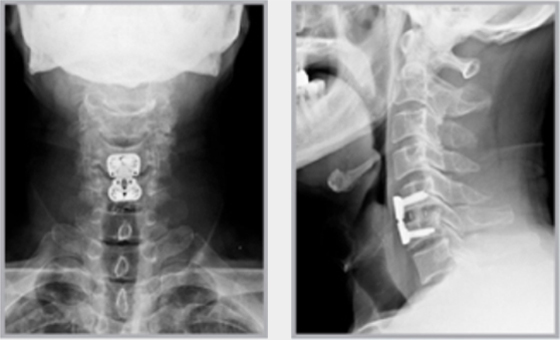

그래서 이러한 생활습관 등으로 인해 목디스크 발병률이 높아질 수 있습니다. 목디스크는 심할 경우 척추 협착증, 척추 손상, 신경 손상, 목뼈의 변형 및 골절 등의 심각한 질환으로 이어질 수 있기 때문에 사전에 미리 예방하는 것이 무엇보다 중요합니다.